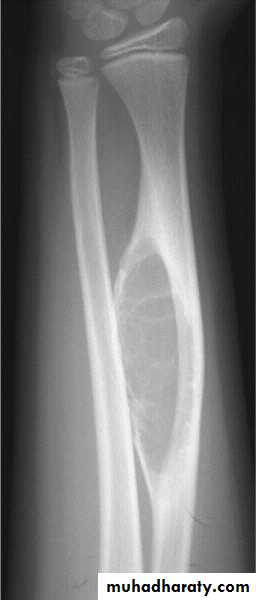

PLANI X-RAY